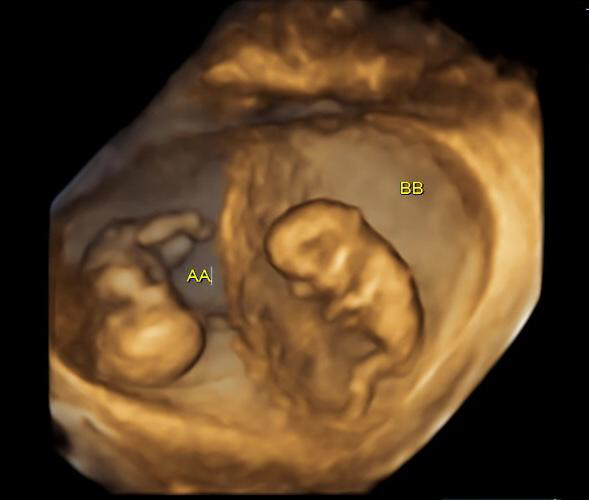

Standard 2D ultrasounds provide basic views of your babies’ positions and growth, but 3D ultrasounds for twins bring an added layer of depth—literally and emotionally. These scans create lifelike, three-dimensional images that let you see facial features, hand movements, and even shared gestures between twins.

With twins often curled up closely in the womb, 3D imaging offers a more detailed and intimate view of their interactions—whether it’s a sibling high-five or simply resting face-to-face.